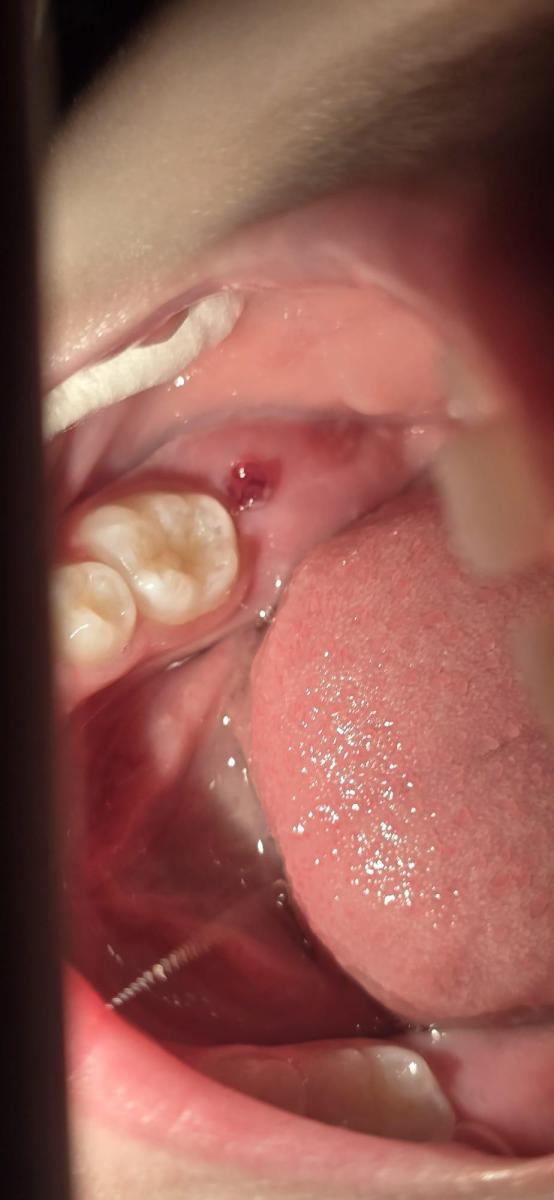

У ребенка 6 лет на жевательной поверхности появилось образование с неровными краями, как выпуклая слизистая ( по типу розы). Какие будут рекомендации учитывая долгие праздничные выходные?

a1ec42c0ccf216493a980e495b79.jpg

Дык, это-ж шестёрка режется! Нормально!